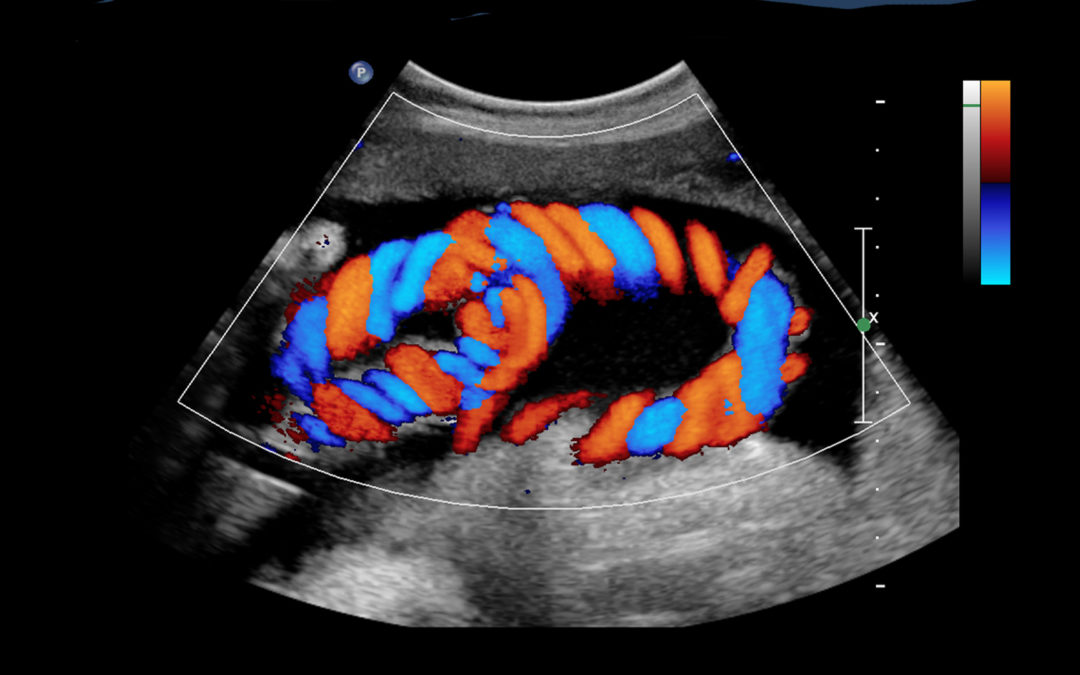

Fetal Dopplers measure the blood flow in different parts of the baby and placenta:

Uterine Artery Doppler: Blood flow from the mother to the uterus

Umbilical Artery Doppler: Blood flow through the umbilical cord

Middle Cerebral Artery Doppler: Blood flow to the baby’s brain

Ductus Venosus Doppler: Blood flow through the baby’s abdomen

These measurements help assess the health and oxygen supply of the baby.